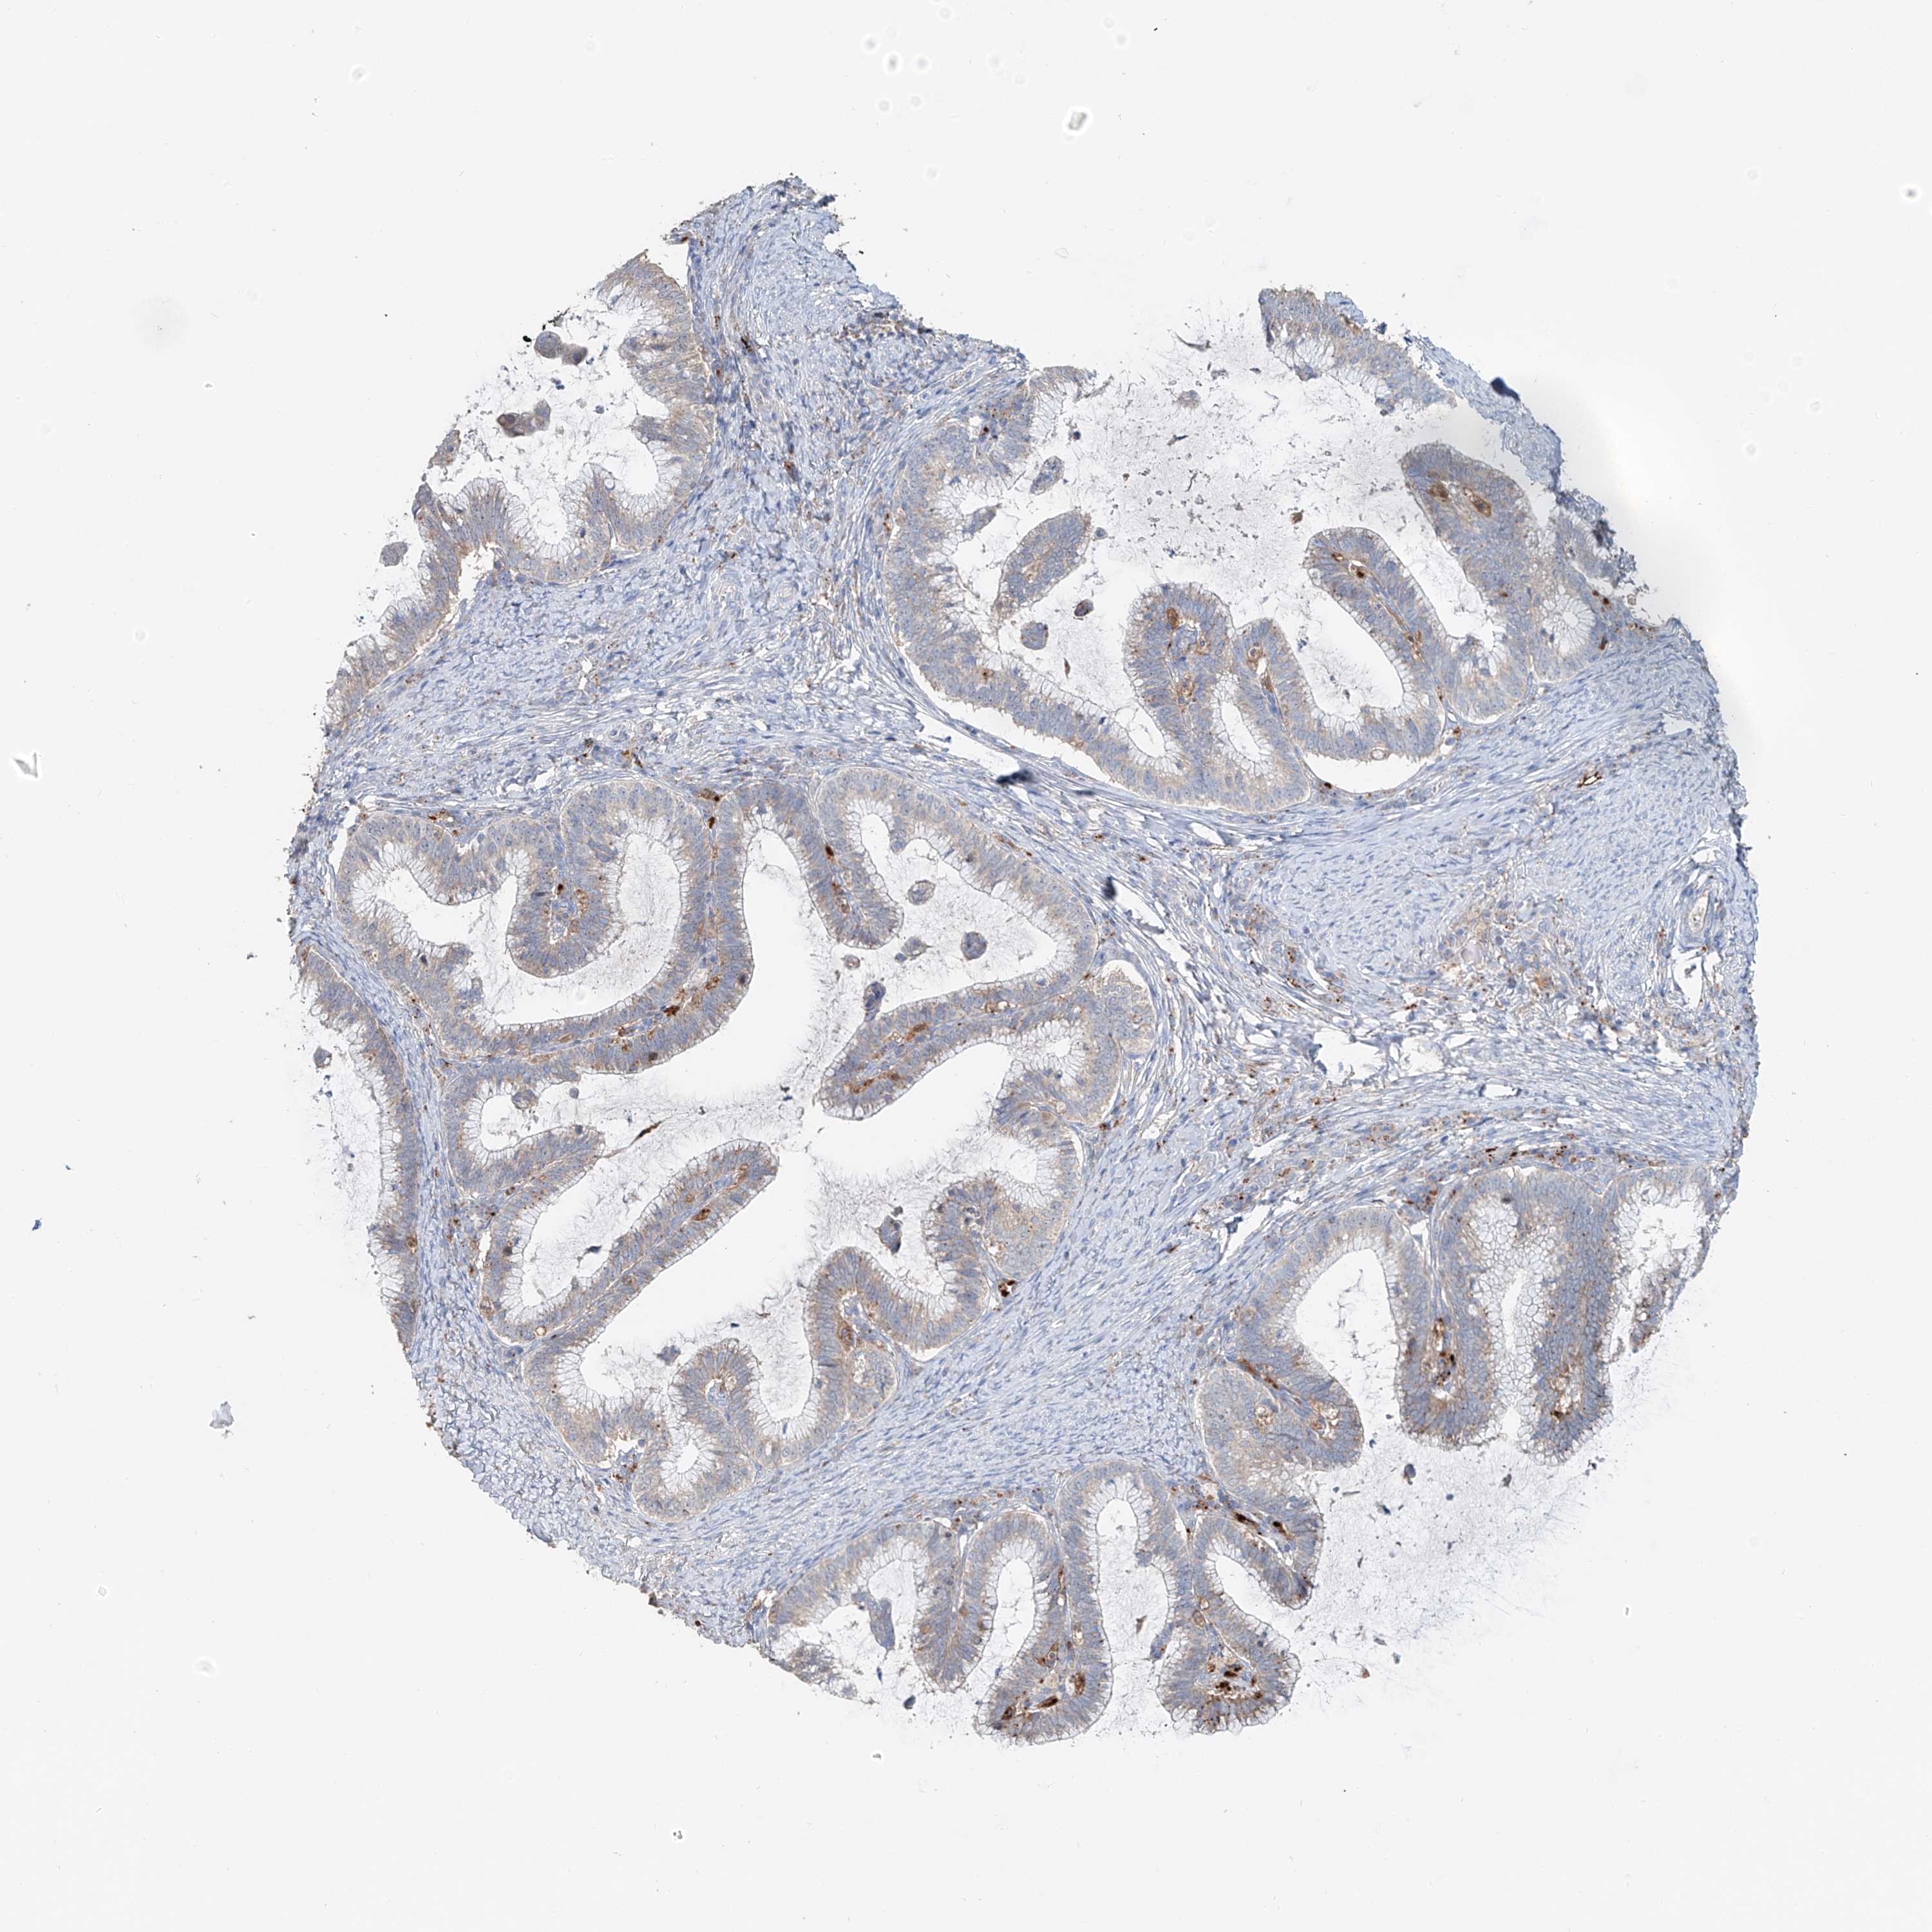

CERVICAL CANCER - Protein expressioni

A mouse-over function shows sample information and annotation data. Click on an image to view it in a full screen mode. Samples can be filtered based on level of antibody staining by selecting one or several of the following categories: high, medium, low and not detected. The assay and annotation is described here.

Note that samples used for immunohistochemistry by the Human Protein Atlas do not correspond to samples in the TCGA dataset.

Antibody stainingi

Antibody staining in the annotated cell types in the current human tissue is reported as not detected, low, medium, or high, based on conventional immunohistochemistry profiling in selected tissues. This score is based on the combination of the staining intensity and fraction of stained cells.

Each image is clickable and will lead to virtual microscopy that enables deeper exploration of all samples and also displays staining intensity scores, fraction scores and subcellular localization as well as patient and tissue information for each sample.

Antibody HPA014933

Staining

High

Medium

Low

Not detected

Intensity

Strong

Moderate

Weak

Negative

Quantity

>75%

75%-25%

<25%

None

Location

Nuclear

Cytoplasmic/membranous

Cytoplasmic/membranous,nuclear

Squamous cell carcinoma, NOS

Adenocarcinoma, NOS